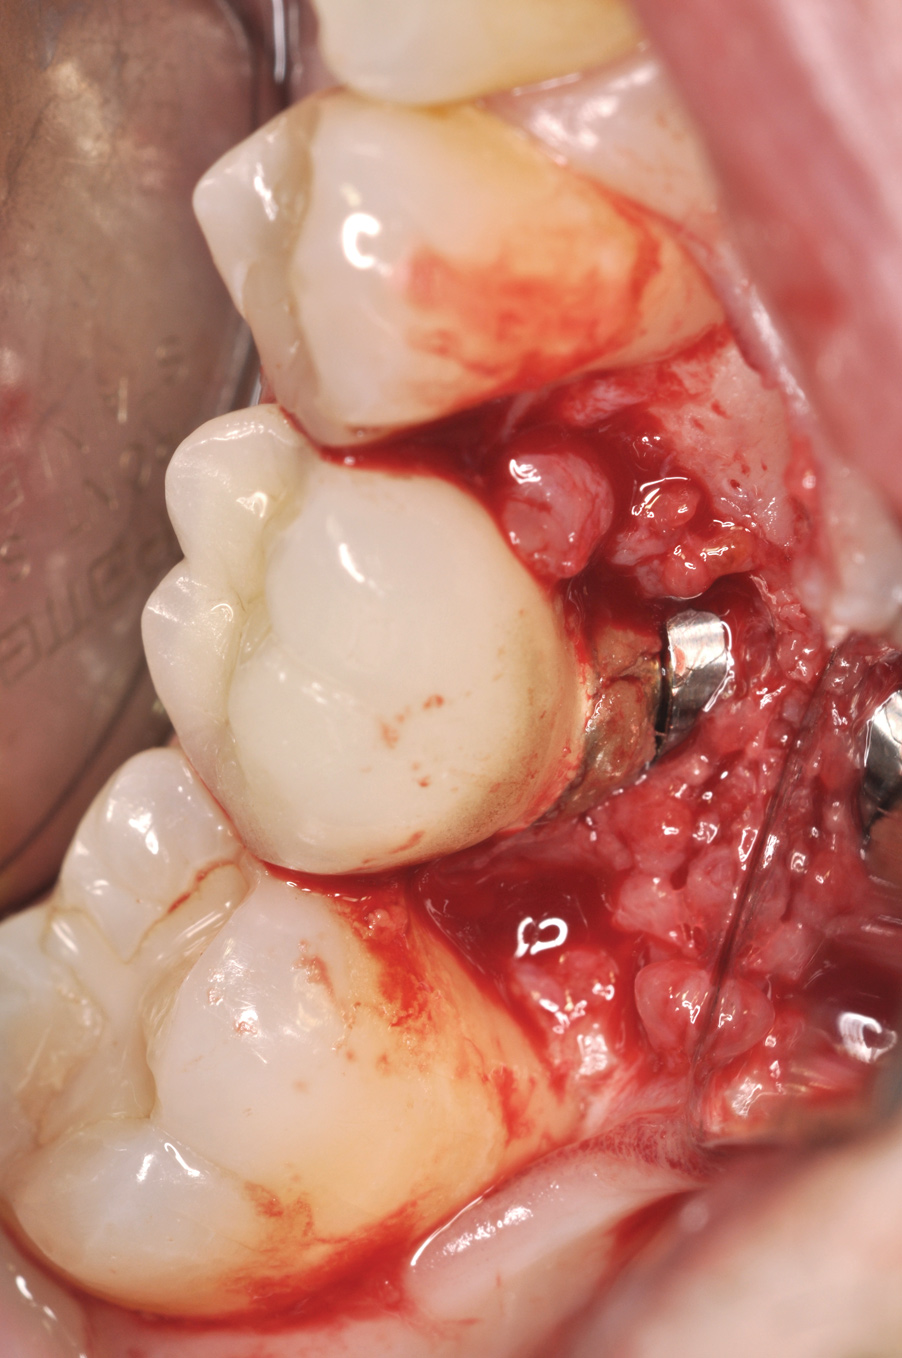

Fig 8. Loss of restoration and subsequent tissue overgrowth from broken abutment screw as shown in the radiograph (Fig 9).

Figure 8